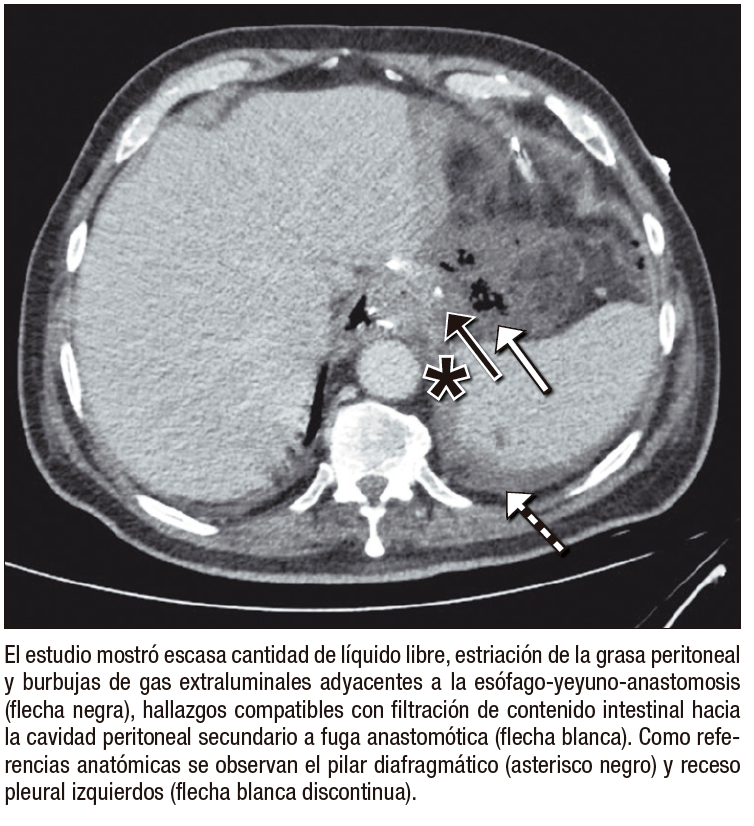

●Caso 1. Hombre de 66 años sometido a gastrectomía total con linfadenectomía por un adenocarcinoma gástrico cardial. En el posoperatorio temprano evolución con dolor abdominal y elevación de los parámetros inflamatorios, por lo que se realizó una TC de abdomen y pelvis en fase porto-venosa que evidenció filtración de la esófago-yeyuno anastomosis, tras lo cual fue intervenido quirúrgicamente, con reparación satisfactoria de la anastomosis.

Entre las complicaciones tempranas, la filtración anastomótica es una de las más graves, con incidencia reportada del 1% – 10% y elevada mortalidad.5 La TC es más sensible que el tránsito baritado para detectar colecciones con gas y extravasación de contraste.6, 7 La hemorragia posoperatoria, aunque infrecuente (0,5% – 5%), constituye una emergencia vital; la TC permite detectar hematomas y extravasación activa en fase arterial.8 La fístula entero-quilosa es poco común y secundaria a lesión linfática durante la linfadenectomía; en TC puede manifestarse como líquido hipodenso o colecciones con nivel líquido-graso.9 La pancreatitis aguda posoperatoria, generalmente relacionada con manipulación quirúrgica o compromiso vascular, puede confirmarse con TC mediante la identificación de necrosis focal y cambios inflamatorios.10 Finalmente, el infarto omental se observa como una masa grasa heterogénea con estriación del tejido adiposo, simulando absceso o recurrencia tumoral.11